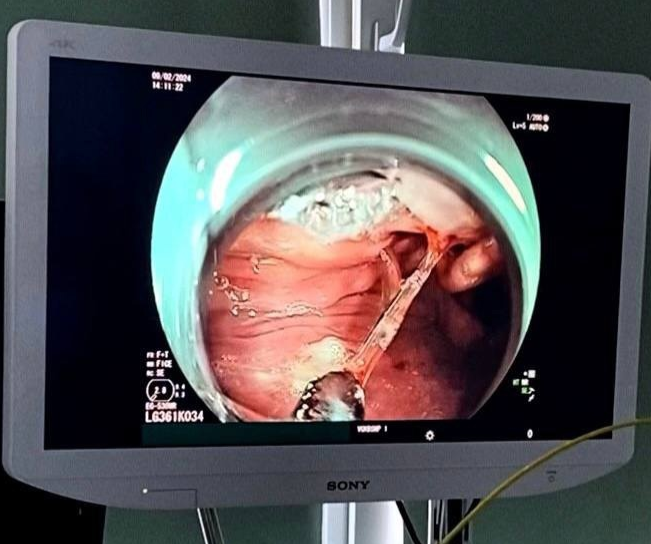

Эндоскопическое выявление и последующее извлечение инородных тел пищевода является одной из основных задач экстренной эндоскопической помощи. При подозрении на инородное тело пищевода показано (желательно в течение 2 - 6 часов от появления симптомов), эндоскопическое вмешательство.

Сотрудники эндоскопического отделения БУЗ ВО "ВГКБСМП№1" в круглосуточном режиме оказывают высококвалифицированную помощь и более 30% случаев в год составляют пациенты с данной патологией. На фото удаление рыбной кости